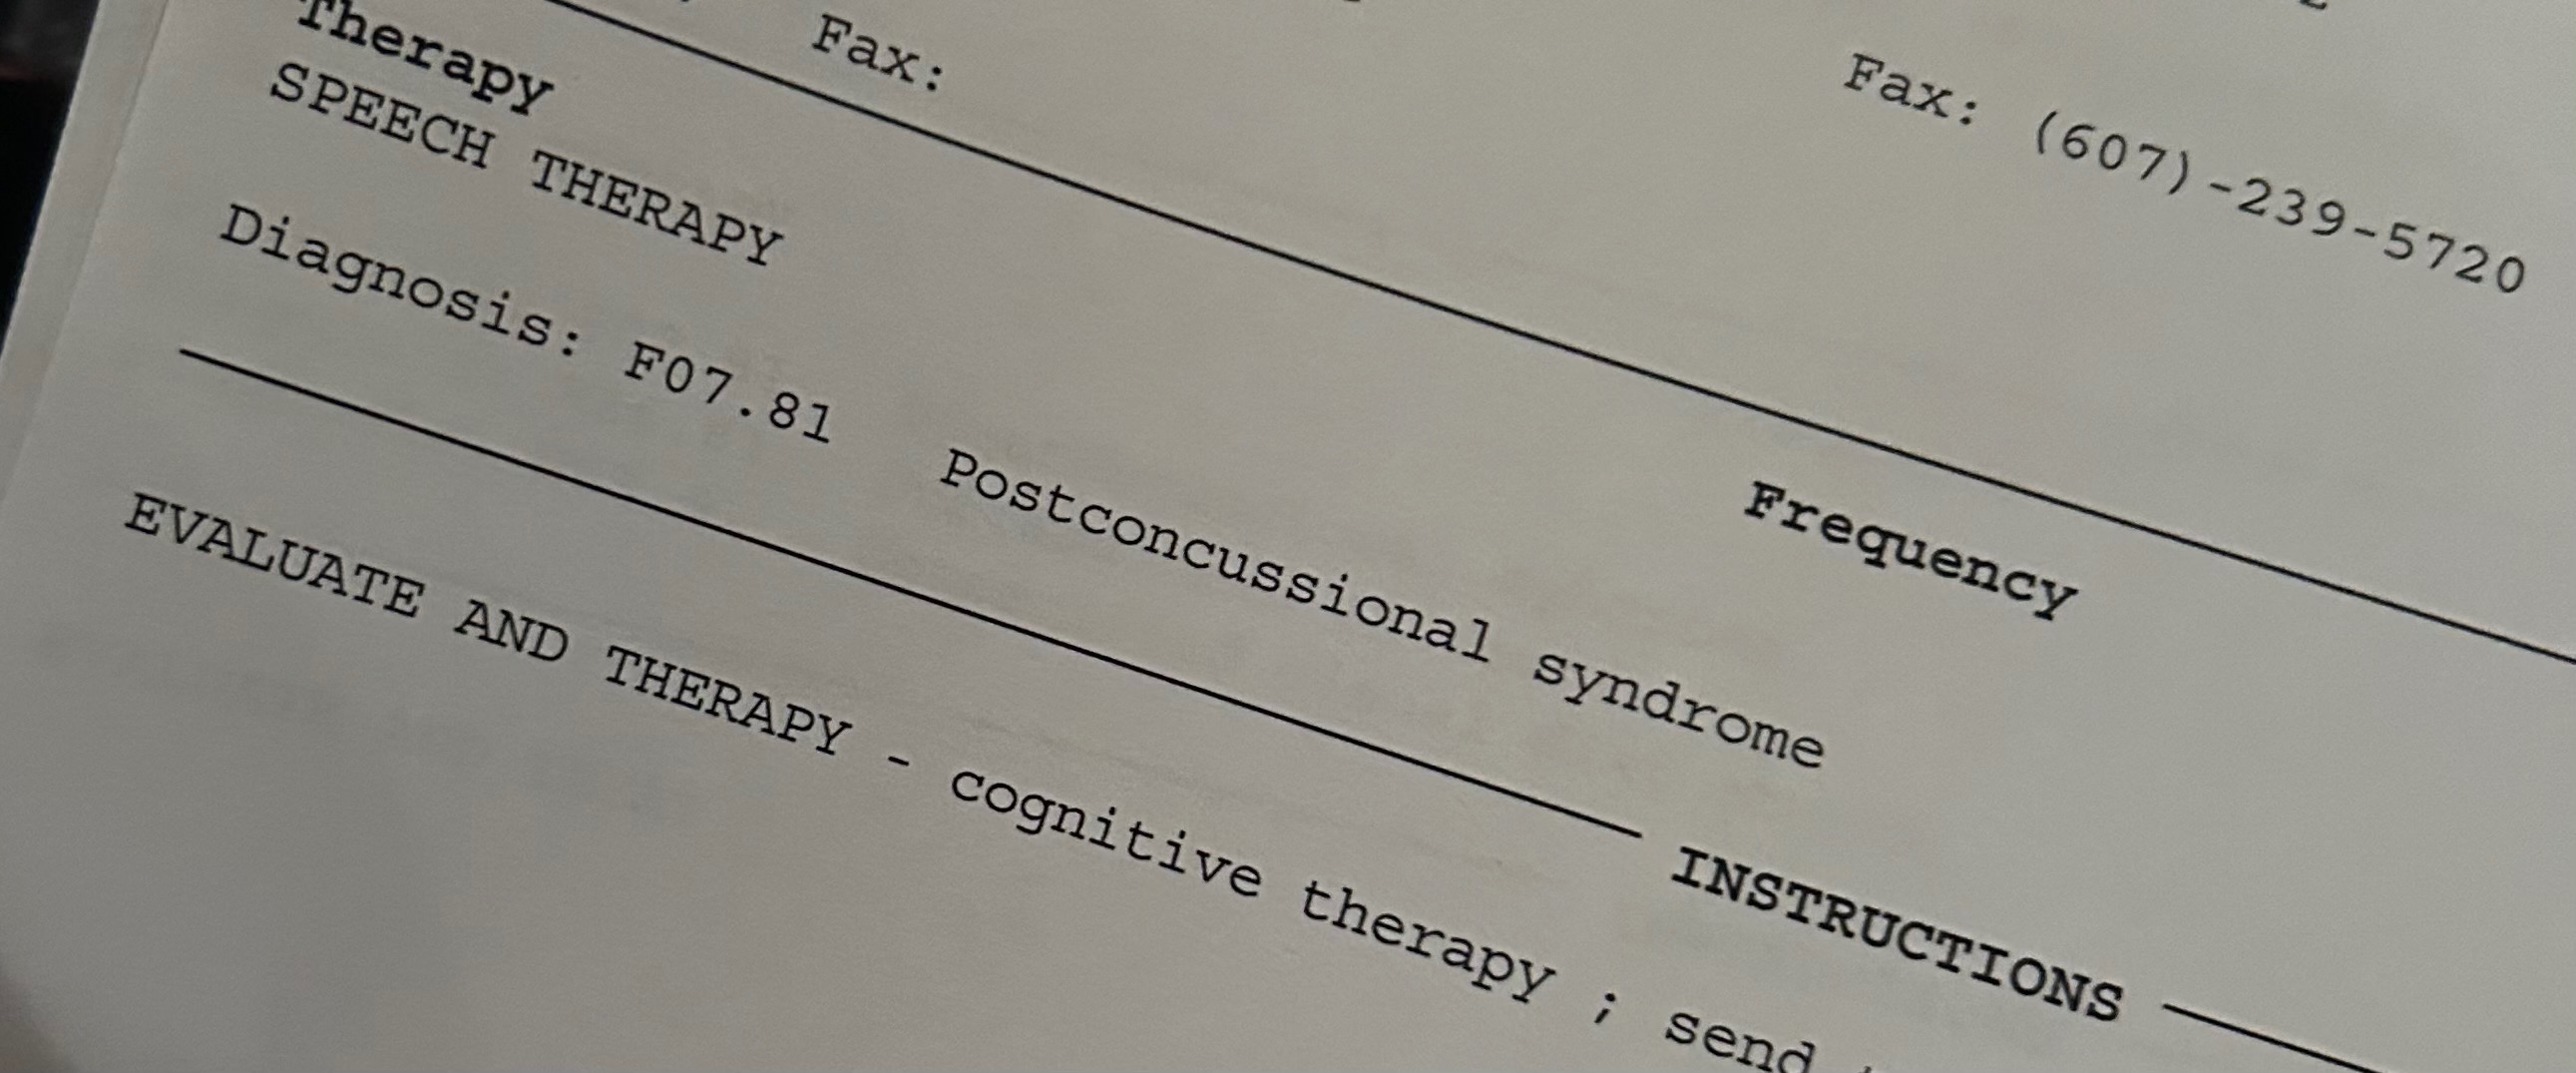

I have no way of predicting when a “good day” will be; most days I am bed bound, sleeping 12-16 hours daily. I also have chronic migraines that require close management, and post concussion syndrome due to head trauma sustained due to a domestic violence related assault in 2024. There is never a time when I am not in pain.

I filed for disability on August 20, 2025. I provided the Social Security Administration with over 300 pages of medical documentation, including x-rays/CT scans/MRI of my spine, head and neck. I submitted all paperwork requested, and had both a medical evaluation and a psychiatric evaluation completed. I was denied on December 2, 2025. At that point, I obtained a lawyer to assist me in appealing the denial. Today I received an email from the Social Security Administration stating that I have been denied a second time.